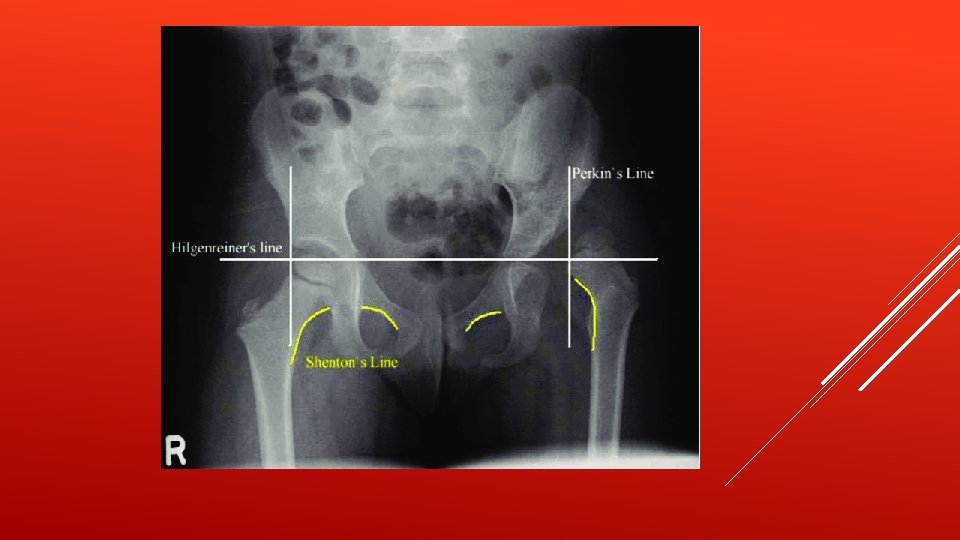

The triradiate cartilage is the 'Y'-shaped epiphyseal plate between the ilium, ischium and pubis to form the acetabulum of the hip bone.